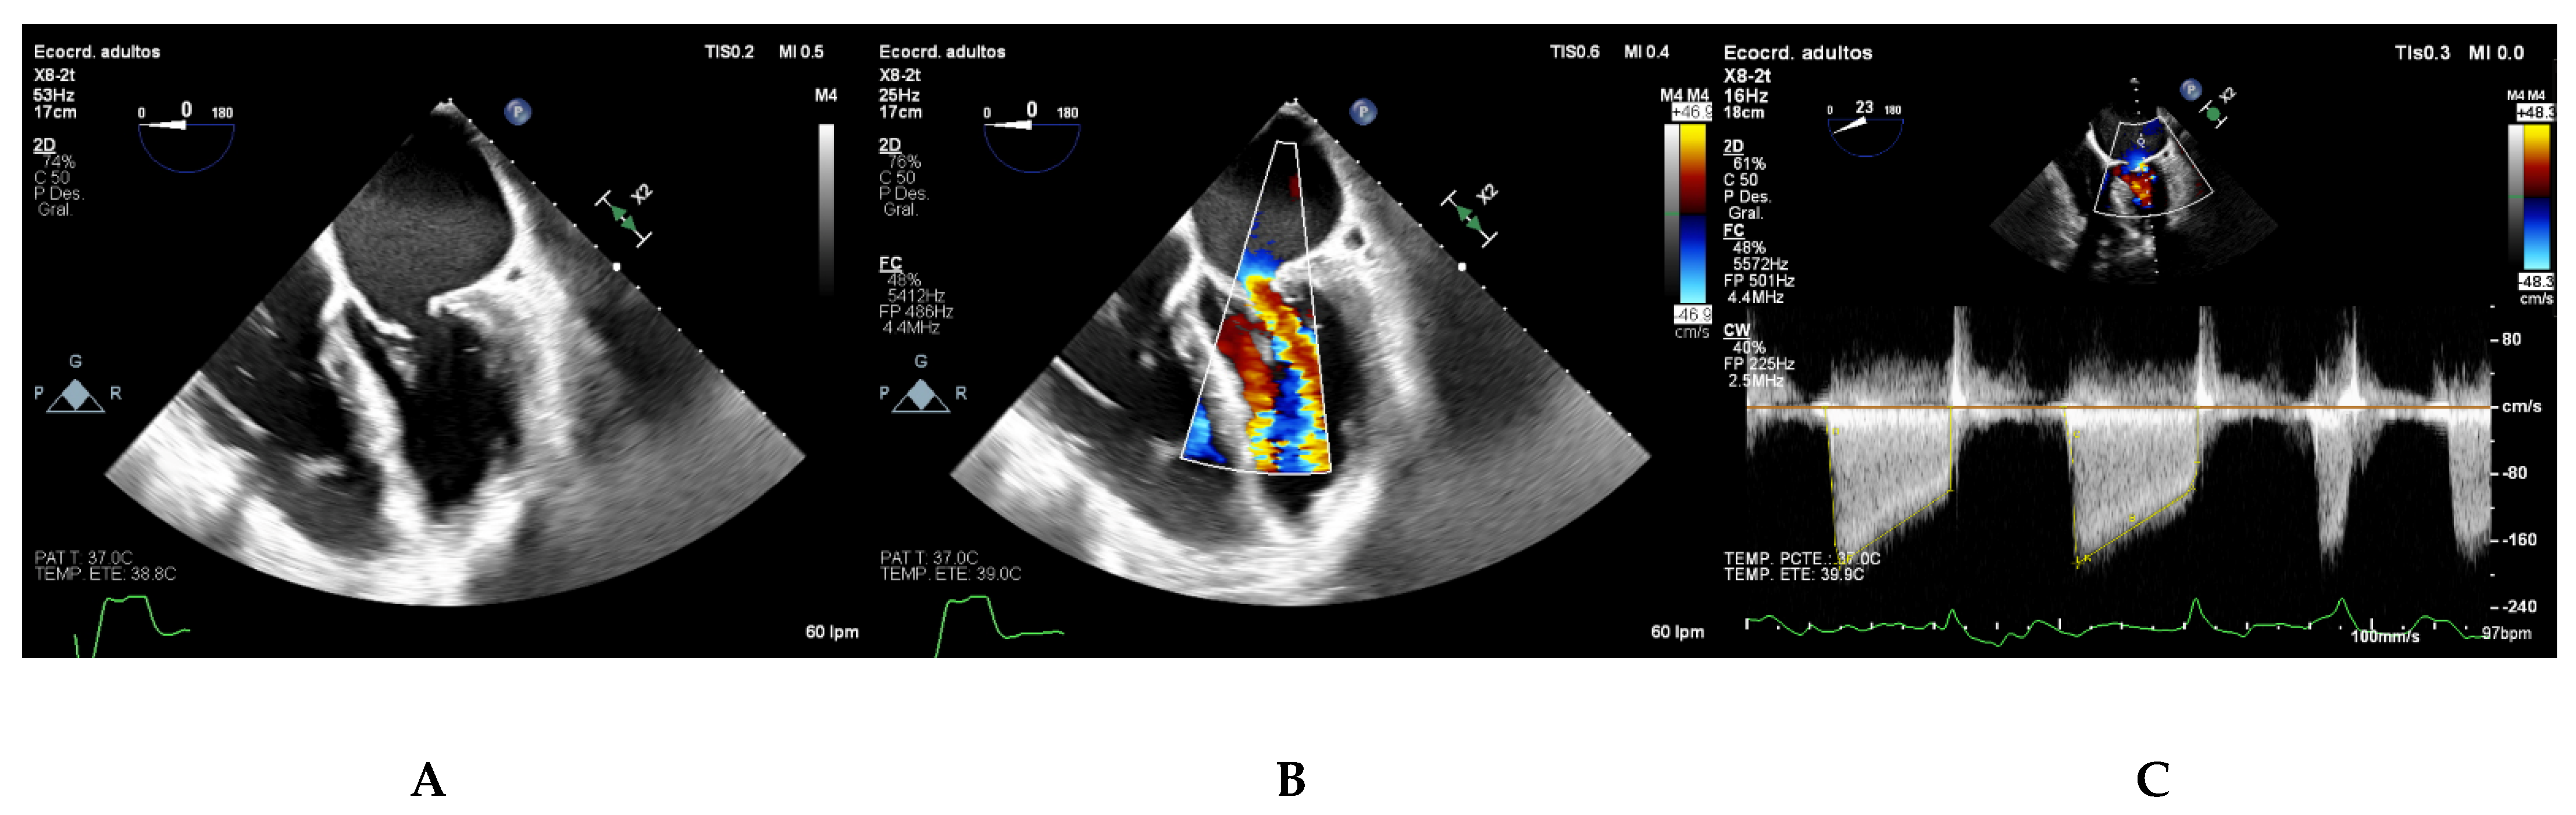

6. Two-Dimensional Transesophageal Echocardiography Assessment